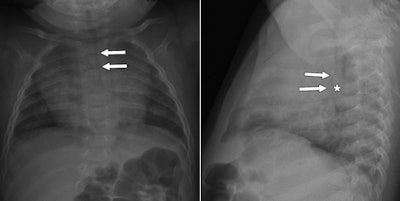

- On all radiographs of the pediatric chest, radiologists should assess the caliber and position of the trachea and the laterality of the aortic arch. These can provide the first clues of the presence of a vascular anomaly.